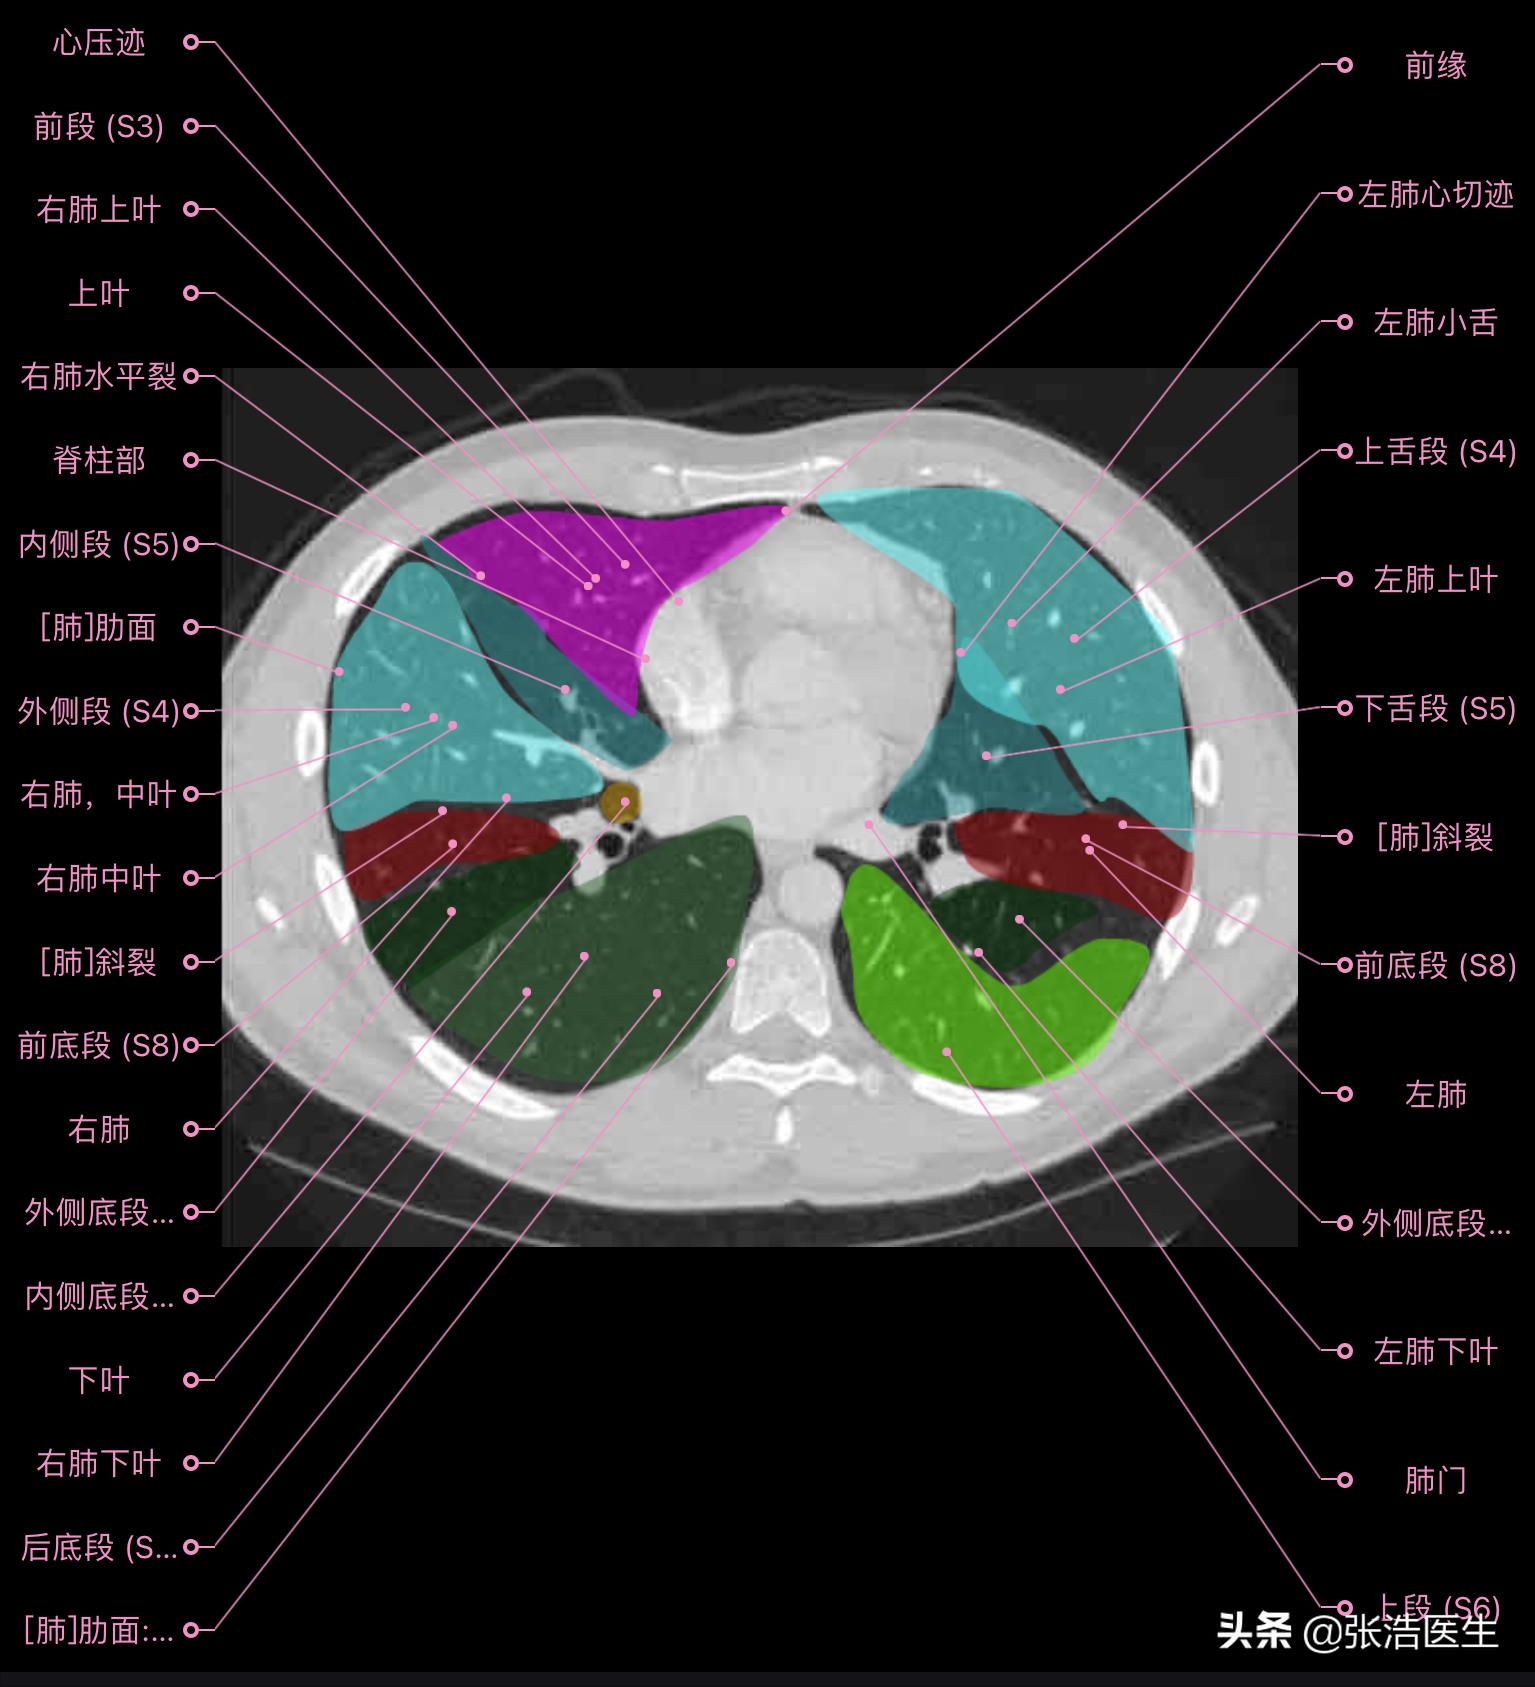

肺部CT横断面高清解剖图谱(图层1)